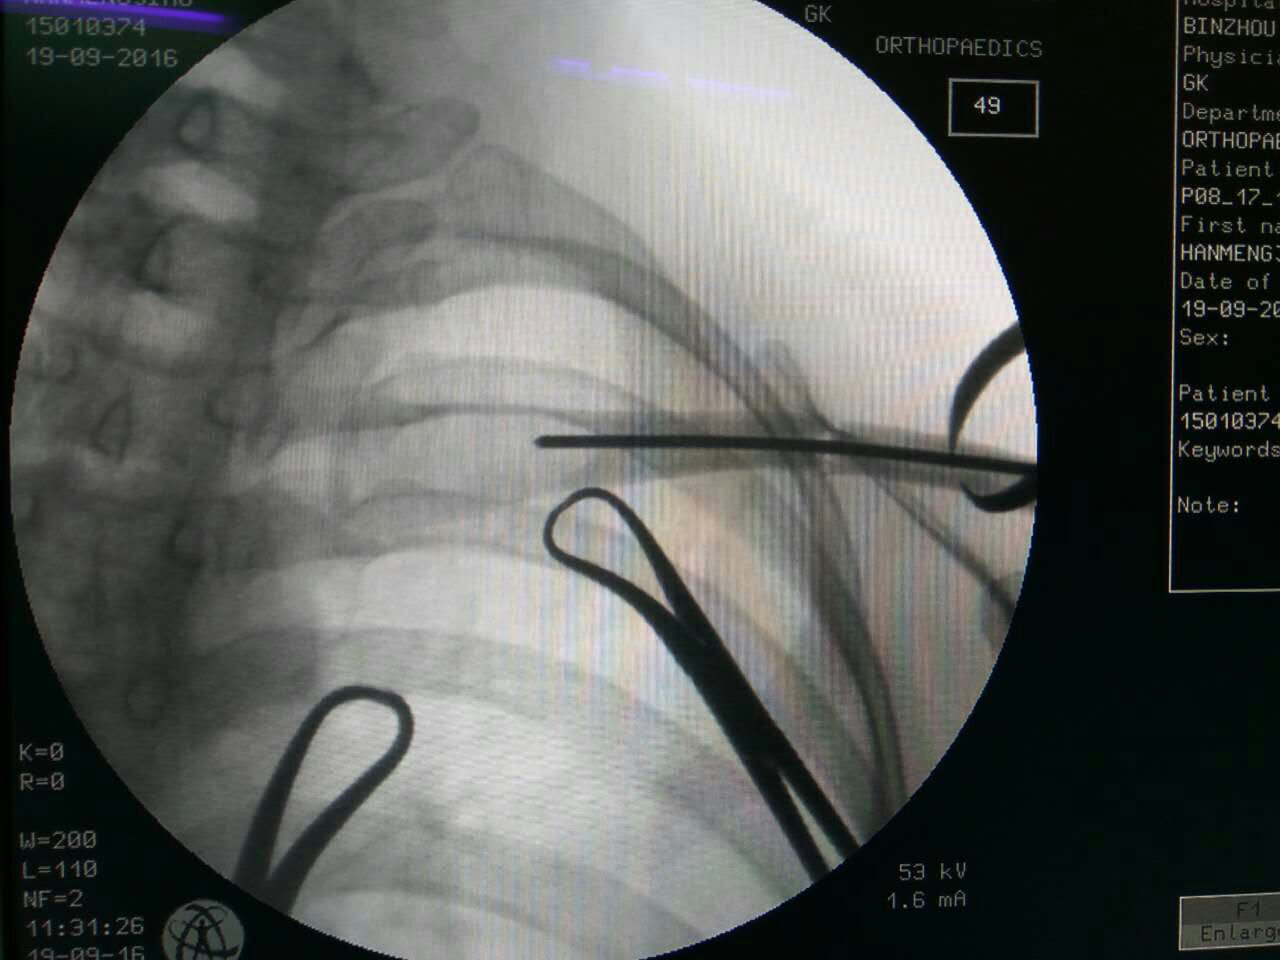

手术由王健民副主任医师、张成勇主治医师、张岭住院医师合作进行。在C型臂X线机的透视下,使用专用锁骨端提钳夹持牵引,中医传统手法复位骨折断端,用2.0mm克氏针穿针固定锁骨。术后,患者的颈肩部仅留下几个细小针眼,愈合后不留疤痕。术后患者十分满意,恢复良好。